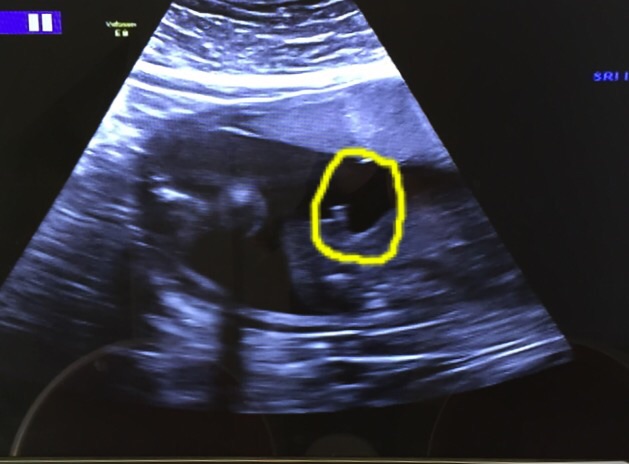

And this one..... What is circled is the penis.... It's a profile shot (bottom half)

Attachment 24130